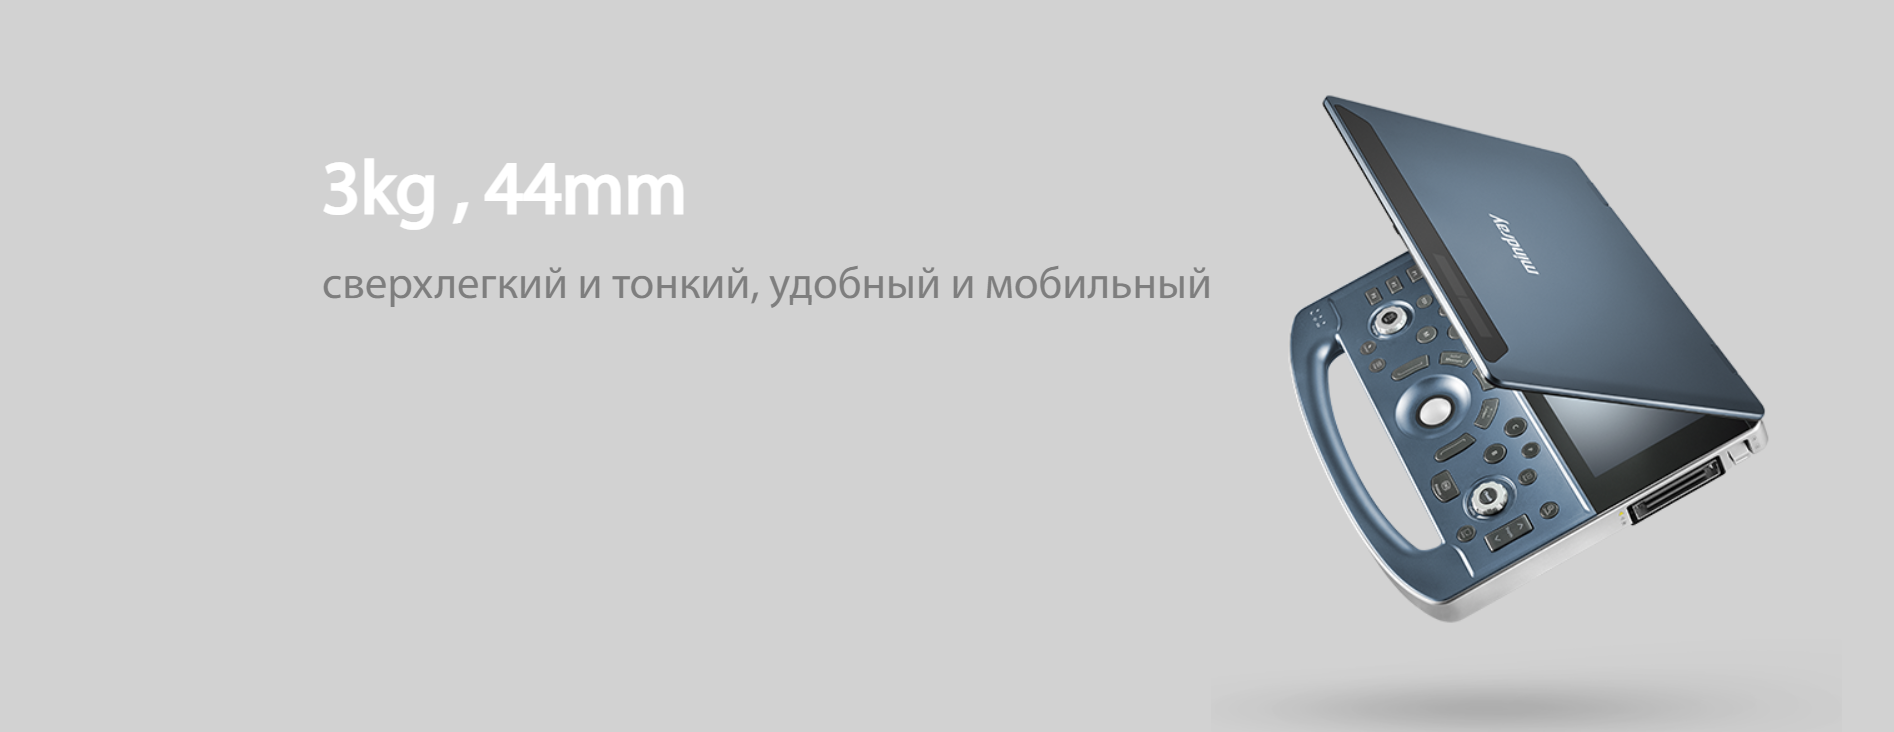

MX7 позволяет проводить точную диагностику на базе передовой платформыZST+ и обеспечивает эффективный рабочий процесс благодаря настраиваемому сенсорному экрану. Ультралегкий корпус и сверхдолгое время работы от аккумулятора (8 ч.) позволяют использовать его в любых клинических условиях (в мобильных госпиталях, на выездах, при исследованиях у кровати больного). Расширенные функции и инструменты анализа для повседневного рутинного применения.

Передовой дизайн